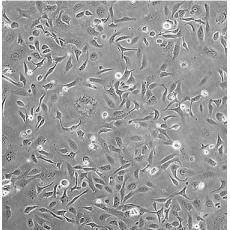

SK-OV-3 [SKOV3]

產品名稱 SK-OV-3 [SKOV3]

中文名稱 人卵巢癌細胞

組織來源 卵巢漿液性囊腺癌;腹水轉移;女性

細胞種屬 Homo sapiens, human

生長特性 adherent

培養基 McCoy's 5A+10% FBS+1% P/S

形態特征 epithelial

細胞描述 SK-OV-3 cells are resistant to tumor necrosis factor and to several cytotoxic drugs including diphtheria toxin, cis-platinum and adriamycin.